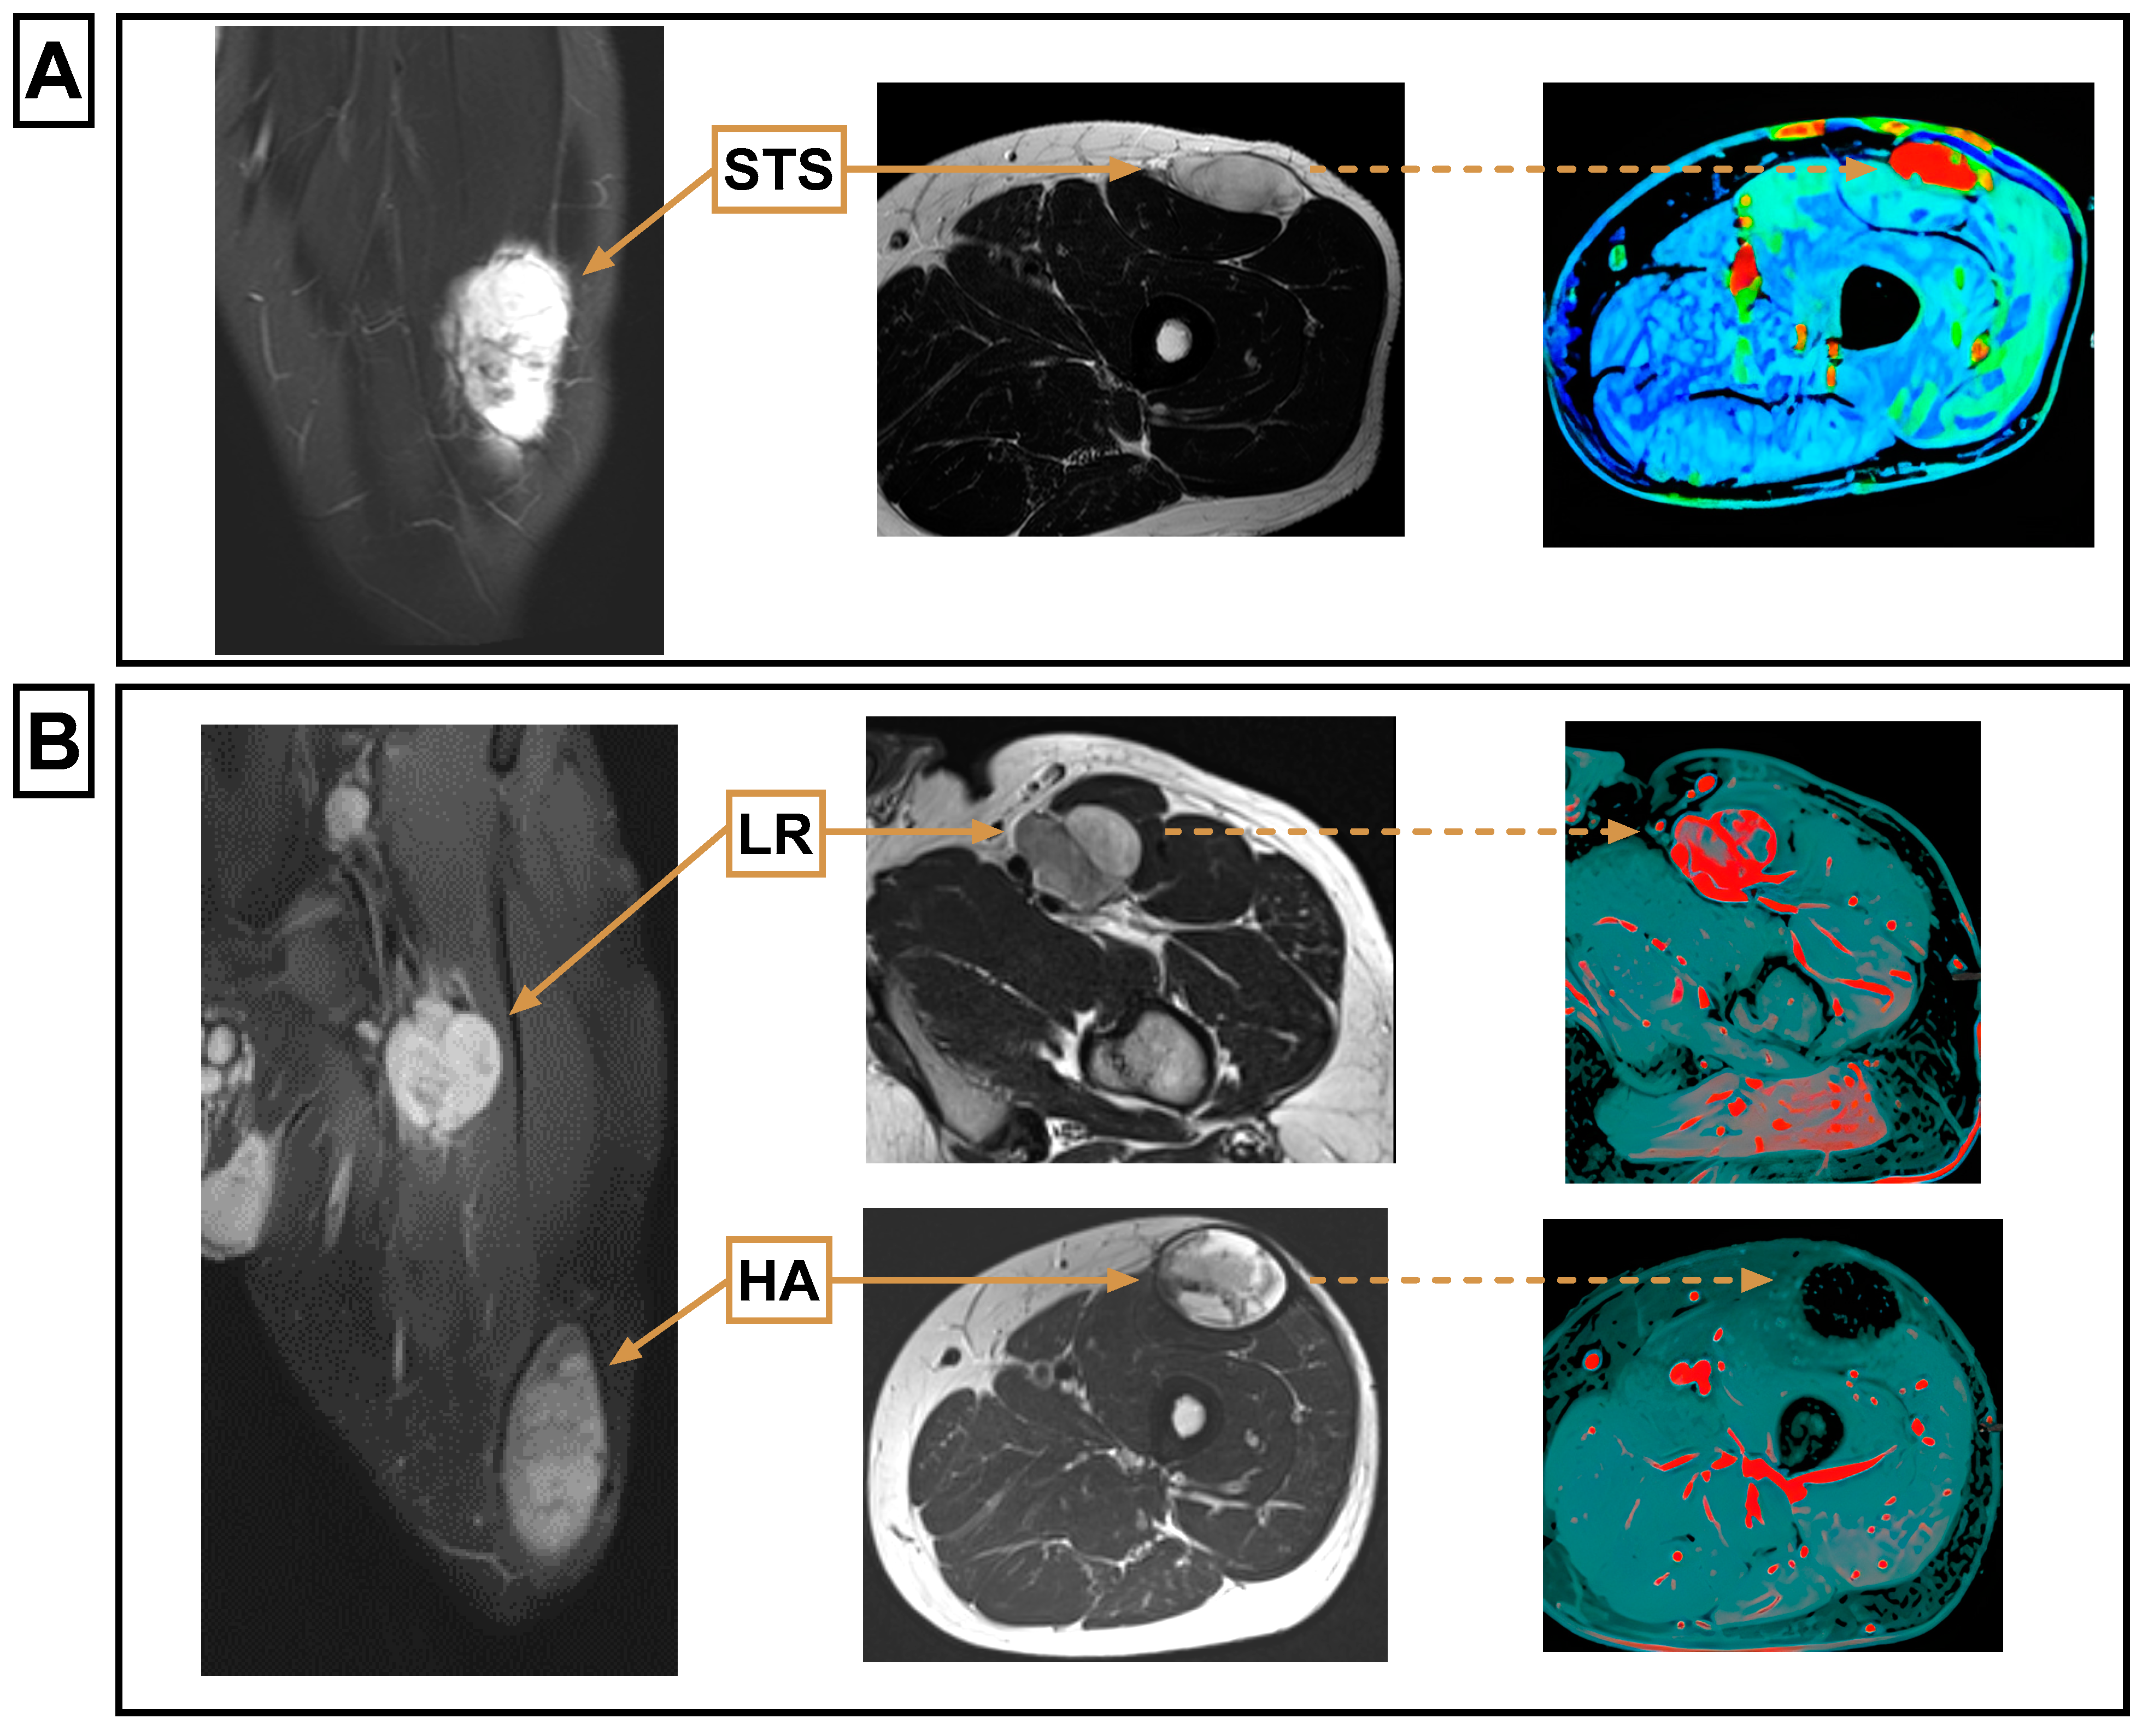

| HA | Hematoma |

| LR | Local recurrence |

| STS | Soft tissue sarcoma |

| Overall MRI feature similarity | Similar to primary STS in all features (26/26) | Differed from primary STS in at least one feature (9/9) | |||